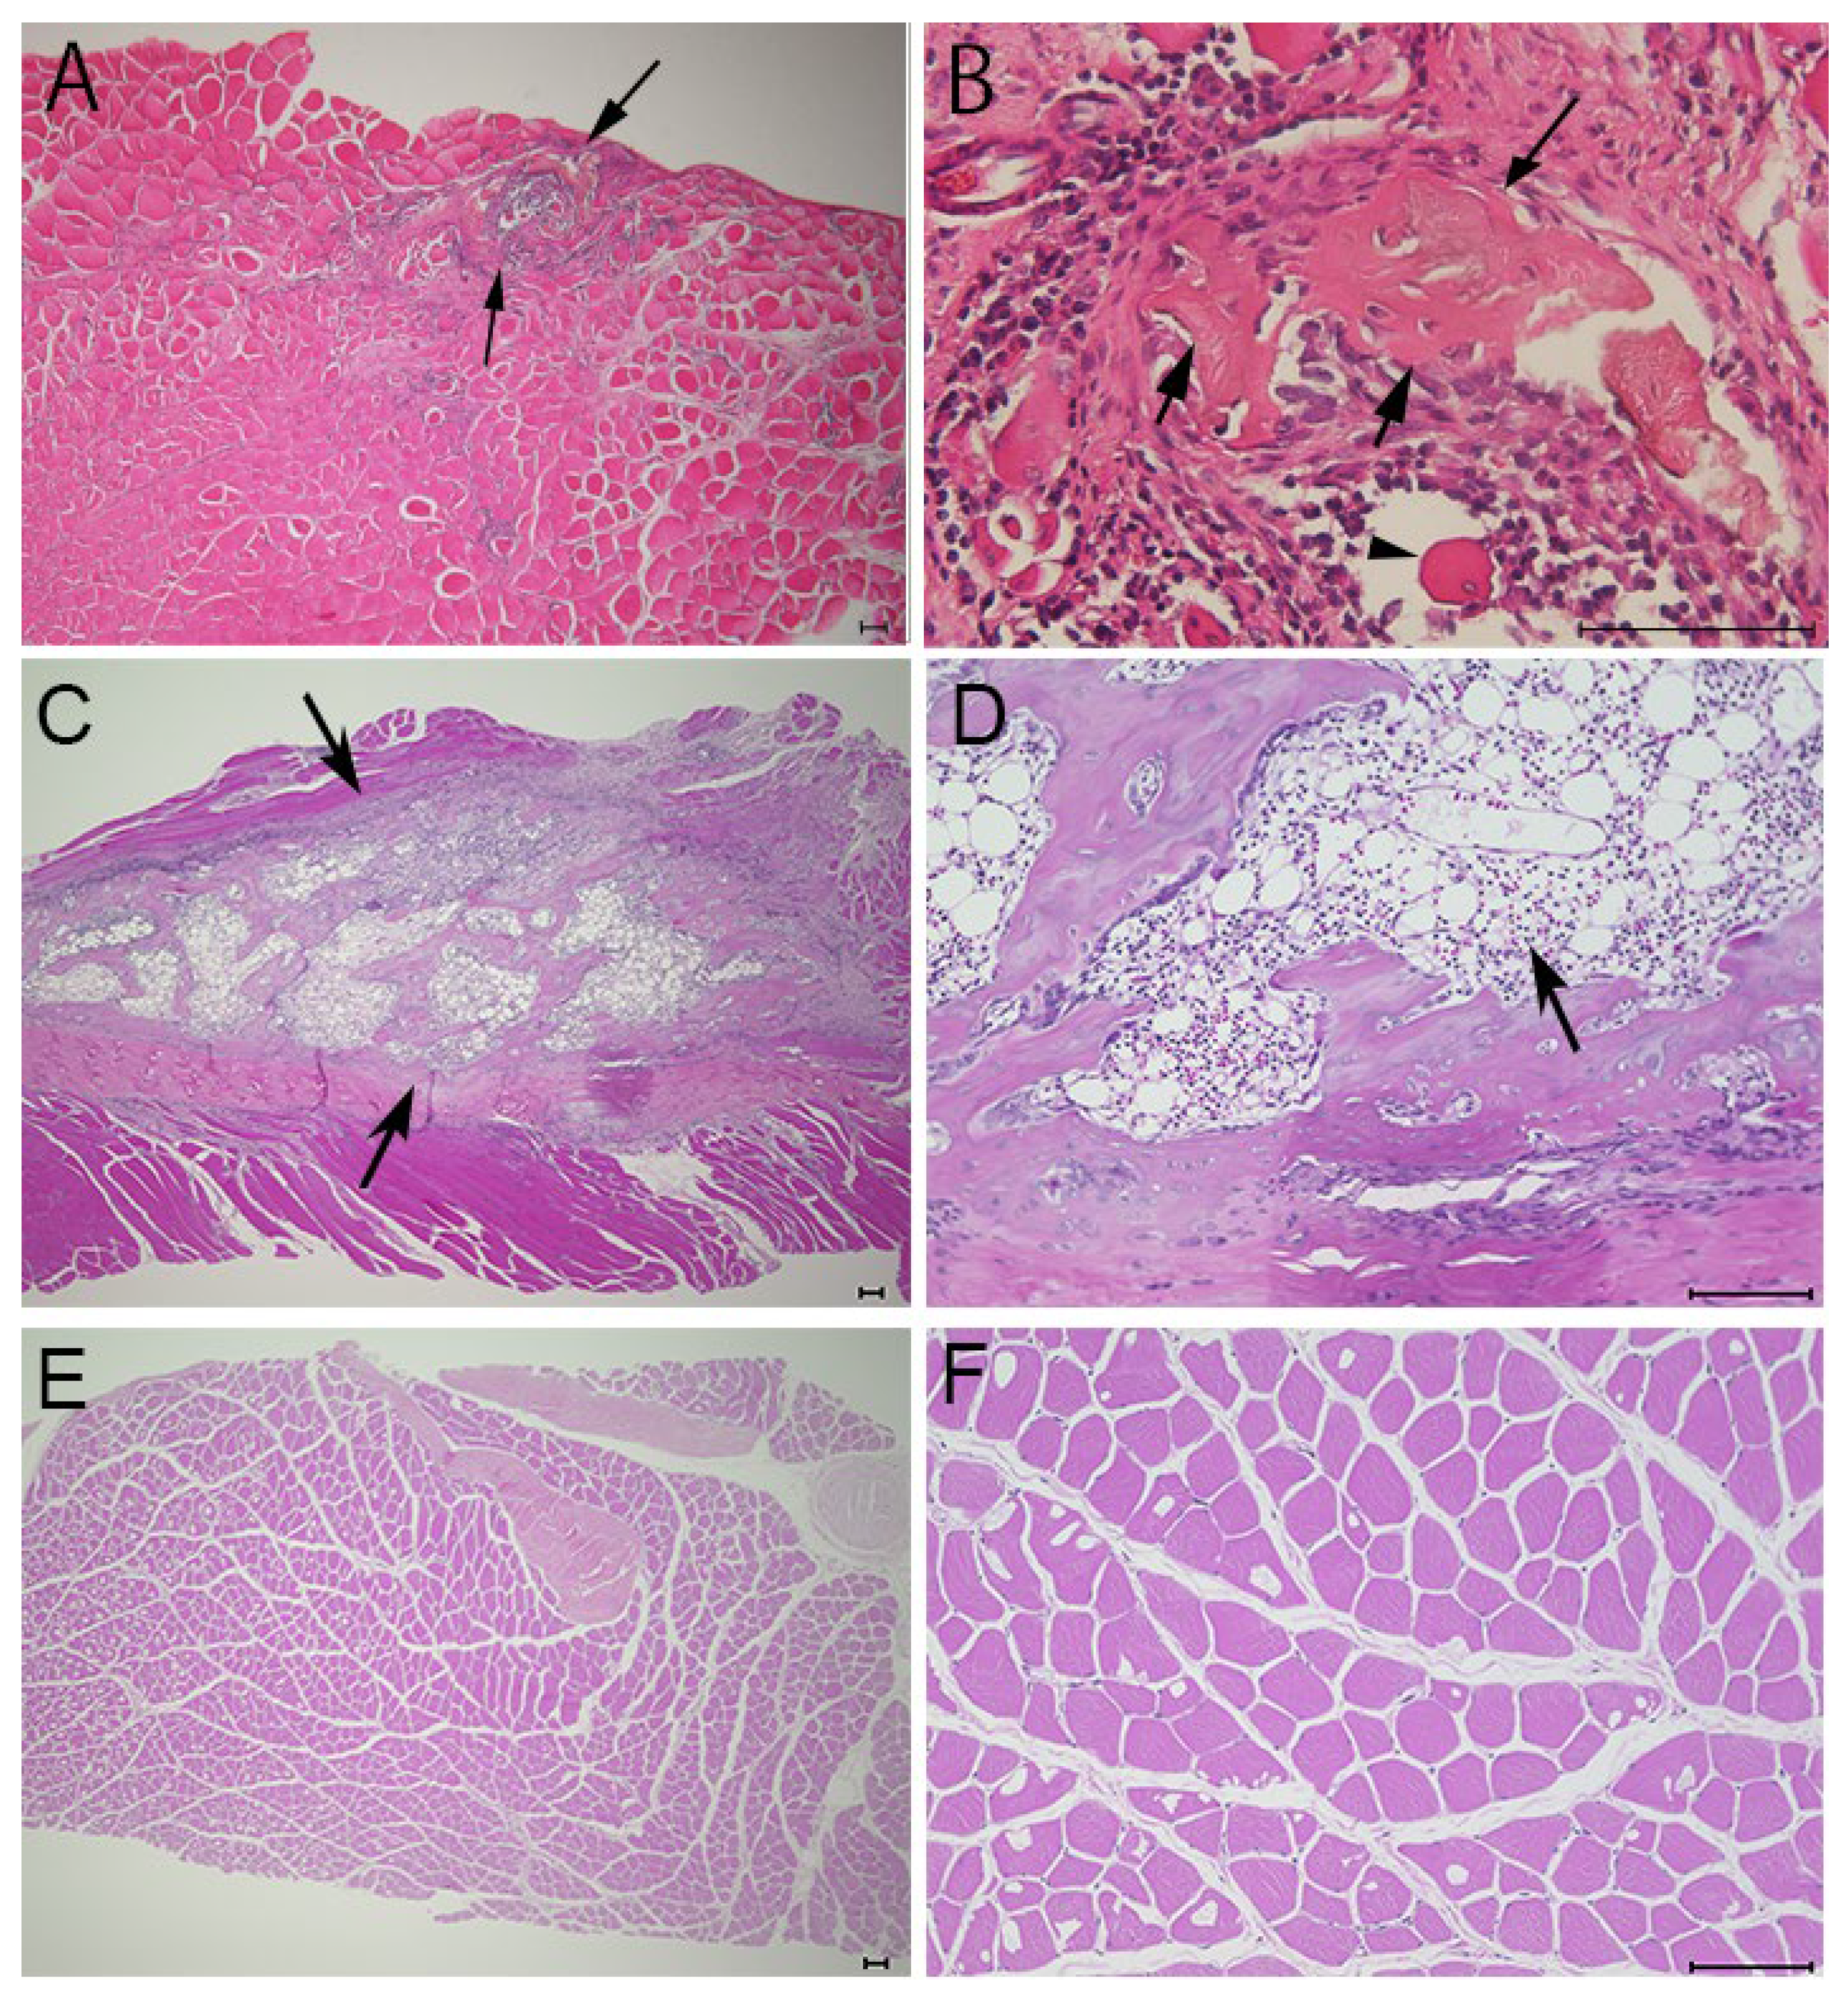

3.2. Histological Findings